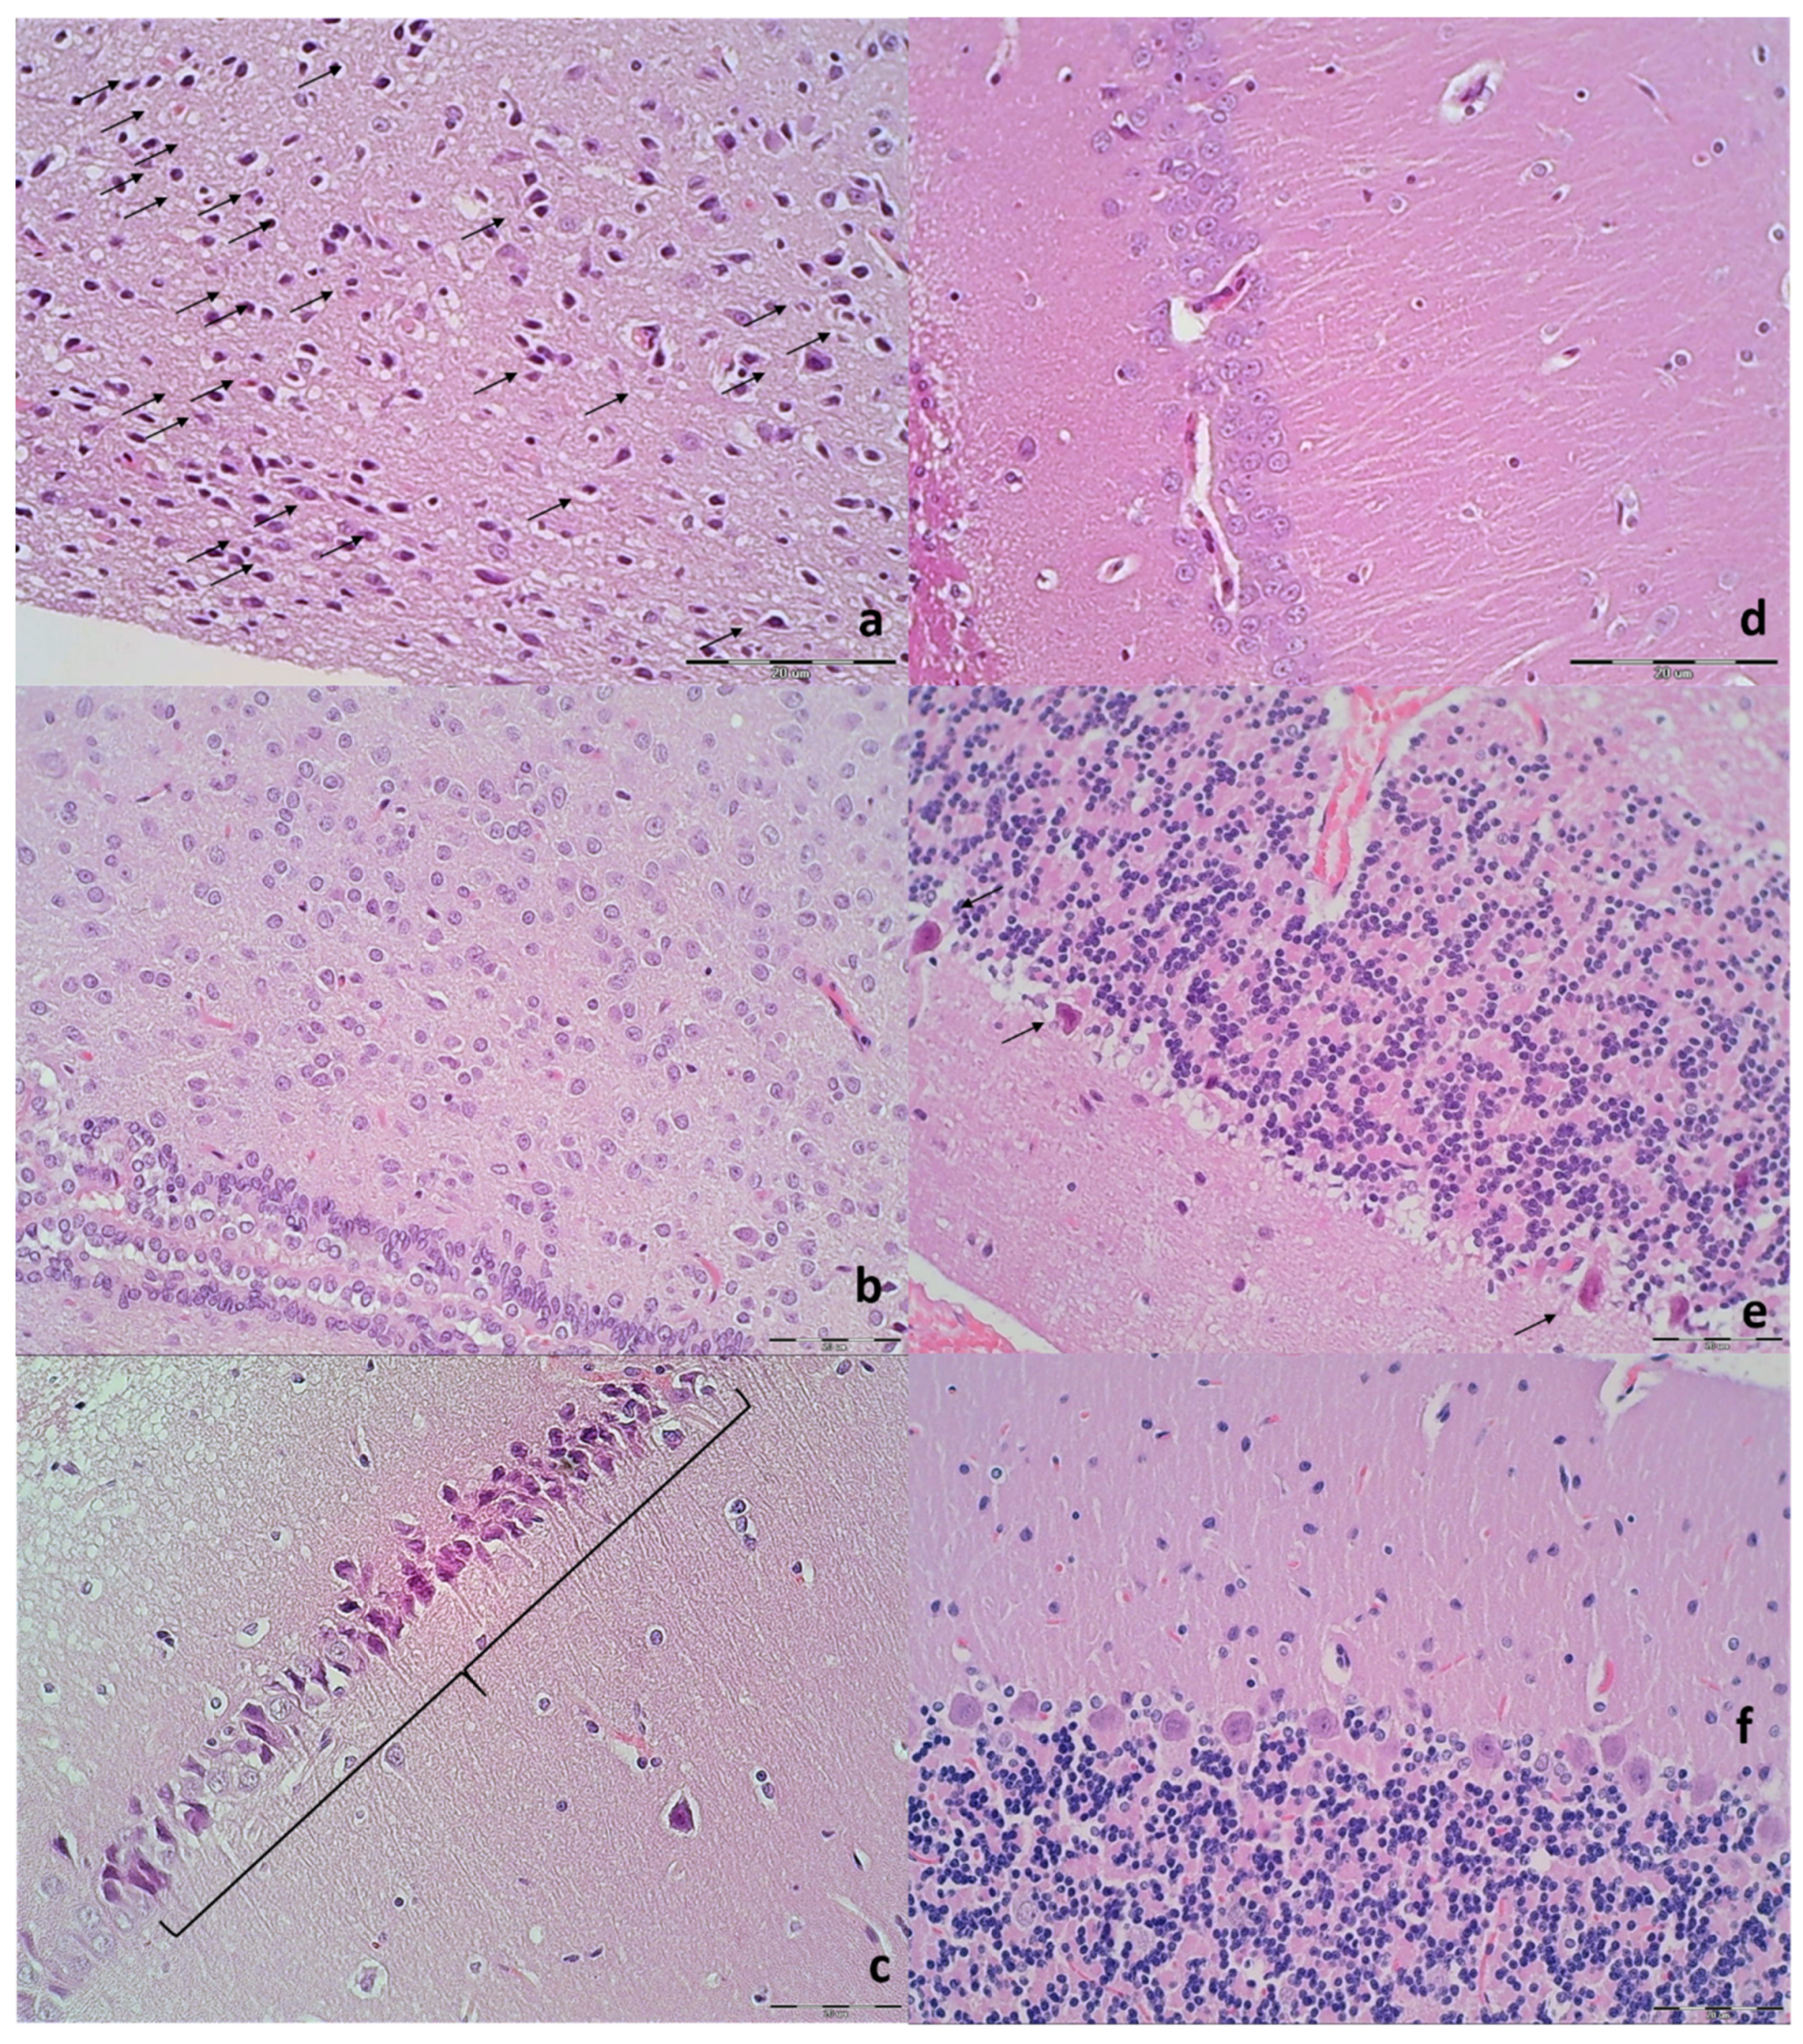

3.9. Histology

| Brain Area | Grading | Percent Area Affected | Morphological Changes |

|---|---|---|---|

| Cerebral and cerebellar cortex, hypothalamus, thalamus, hippocampus | 1 | ≤10 | Small, patchy, complete or incomplete infarcts |

| 2 | 20–30 | Partly confluent complete or incomplete infarcts | |

| 3 | 40–60 | Large confluent compete infarcts | |

| 4 | >75 | In cortex; total disintegration of the tissue, in hypothalamus, thalamus, hippocampus; large complete infarcts | |

| Cerebral and cerebellar cortex, hypothalamus, thalamus, hippocampus | 1 | ≤20 | A few karyopyknotic of neuronal cells |

| 2 | 50 | Patchy areas of karyopyknotic areas | |

| 3 | 75 | More extensive of karyopyknotic areas | |

| 4 | 100 | Complete infarction |